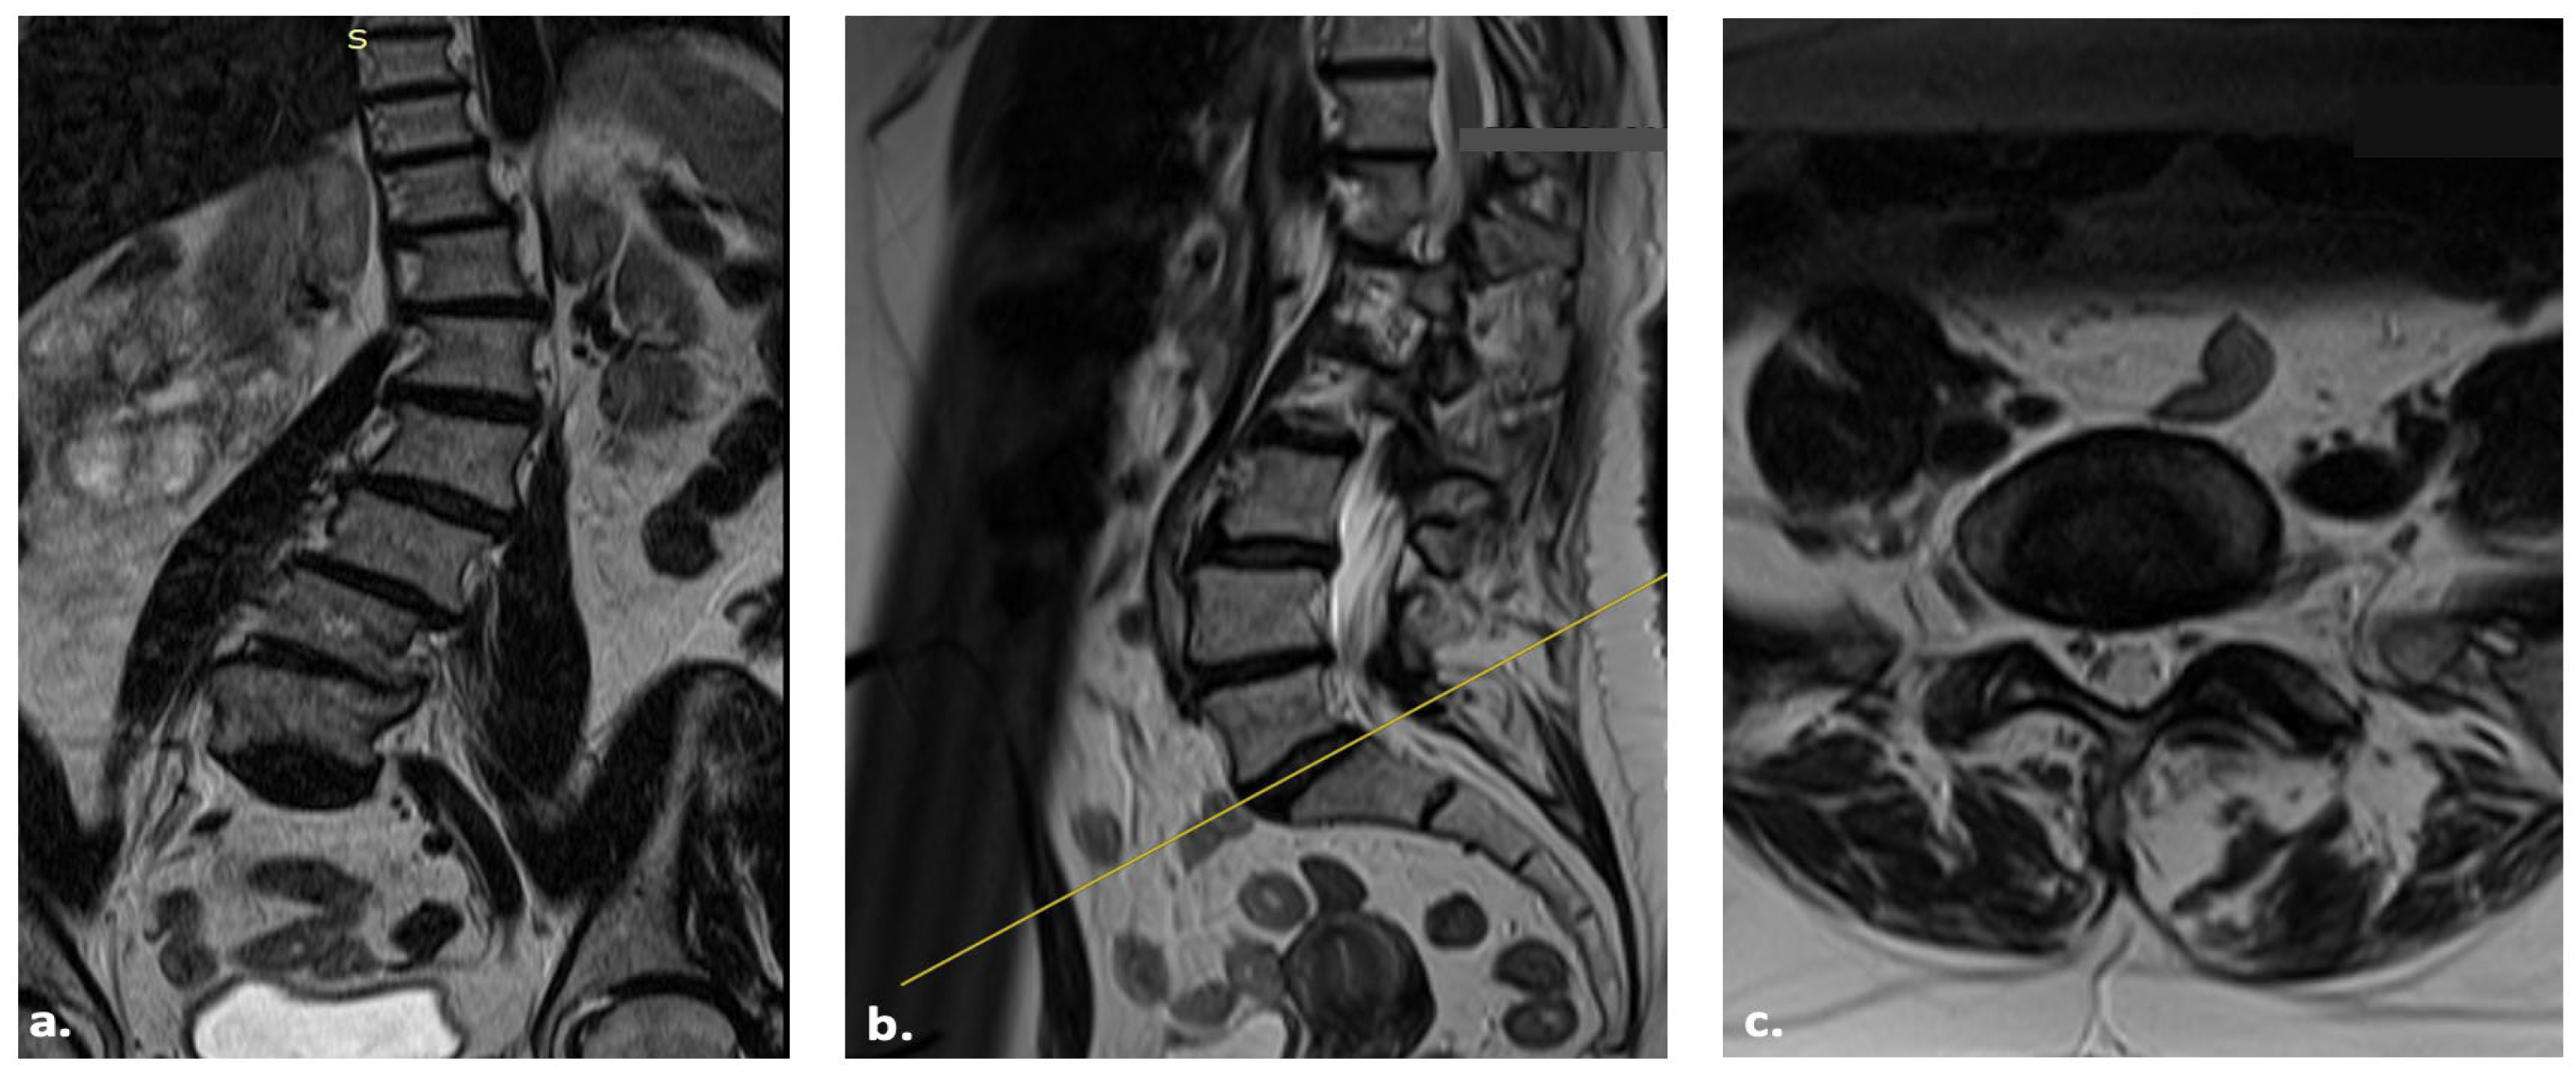

3. Case Report

| Velluto et al., this study | 2024 | 1 | 61 y, F | 1 | Hypertension, Asthma | T4 pelvis for ASD | Complete resolution |